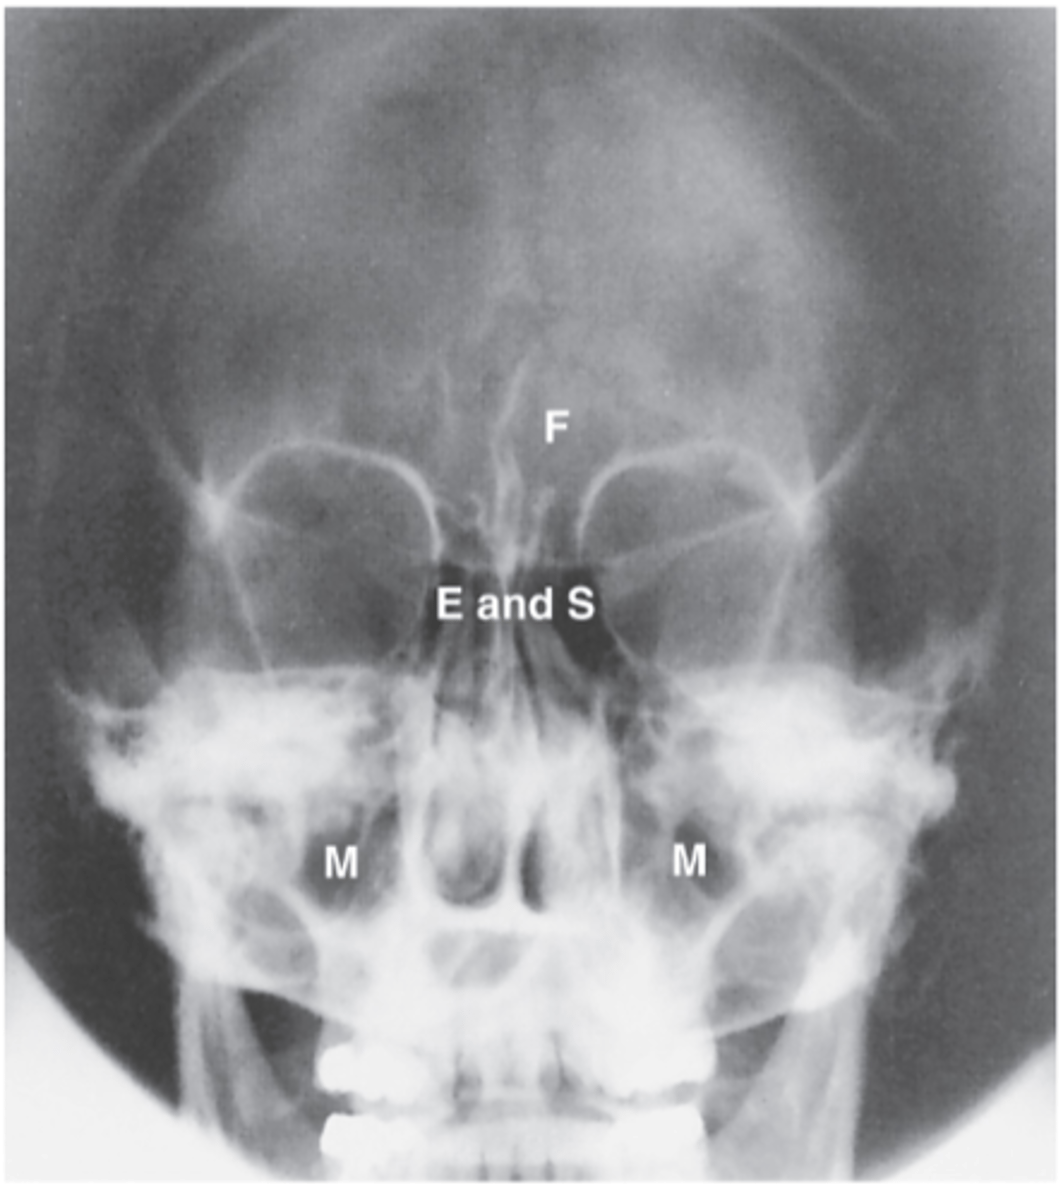

Ethmoid Sinus

E

Sphenoid Sinus

S

Maxillary Sinus

M

Frontal Sinus

F

Lateral Sinuses

What projection is this?

Midway between the EAM and the outer canthus

What is the CR for Lateral Sinuses?

Ethmoid

Sphenoid

Frontal

Maxillary

What sinuses are demonstrated on a Lateral sinuses radiograph?